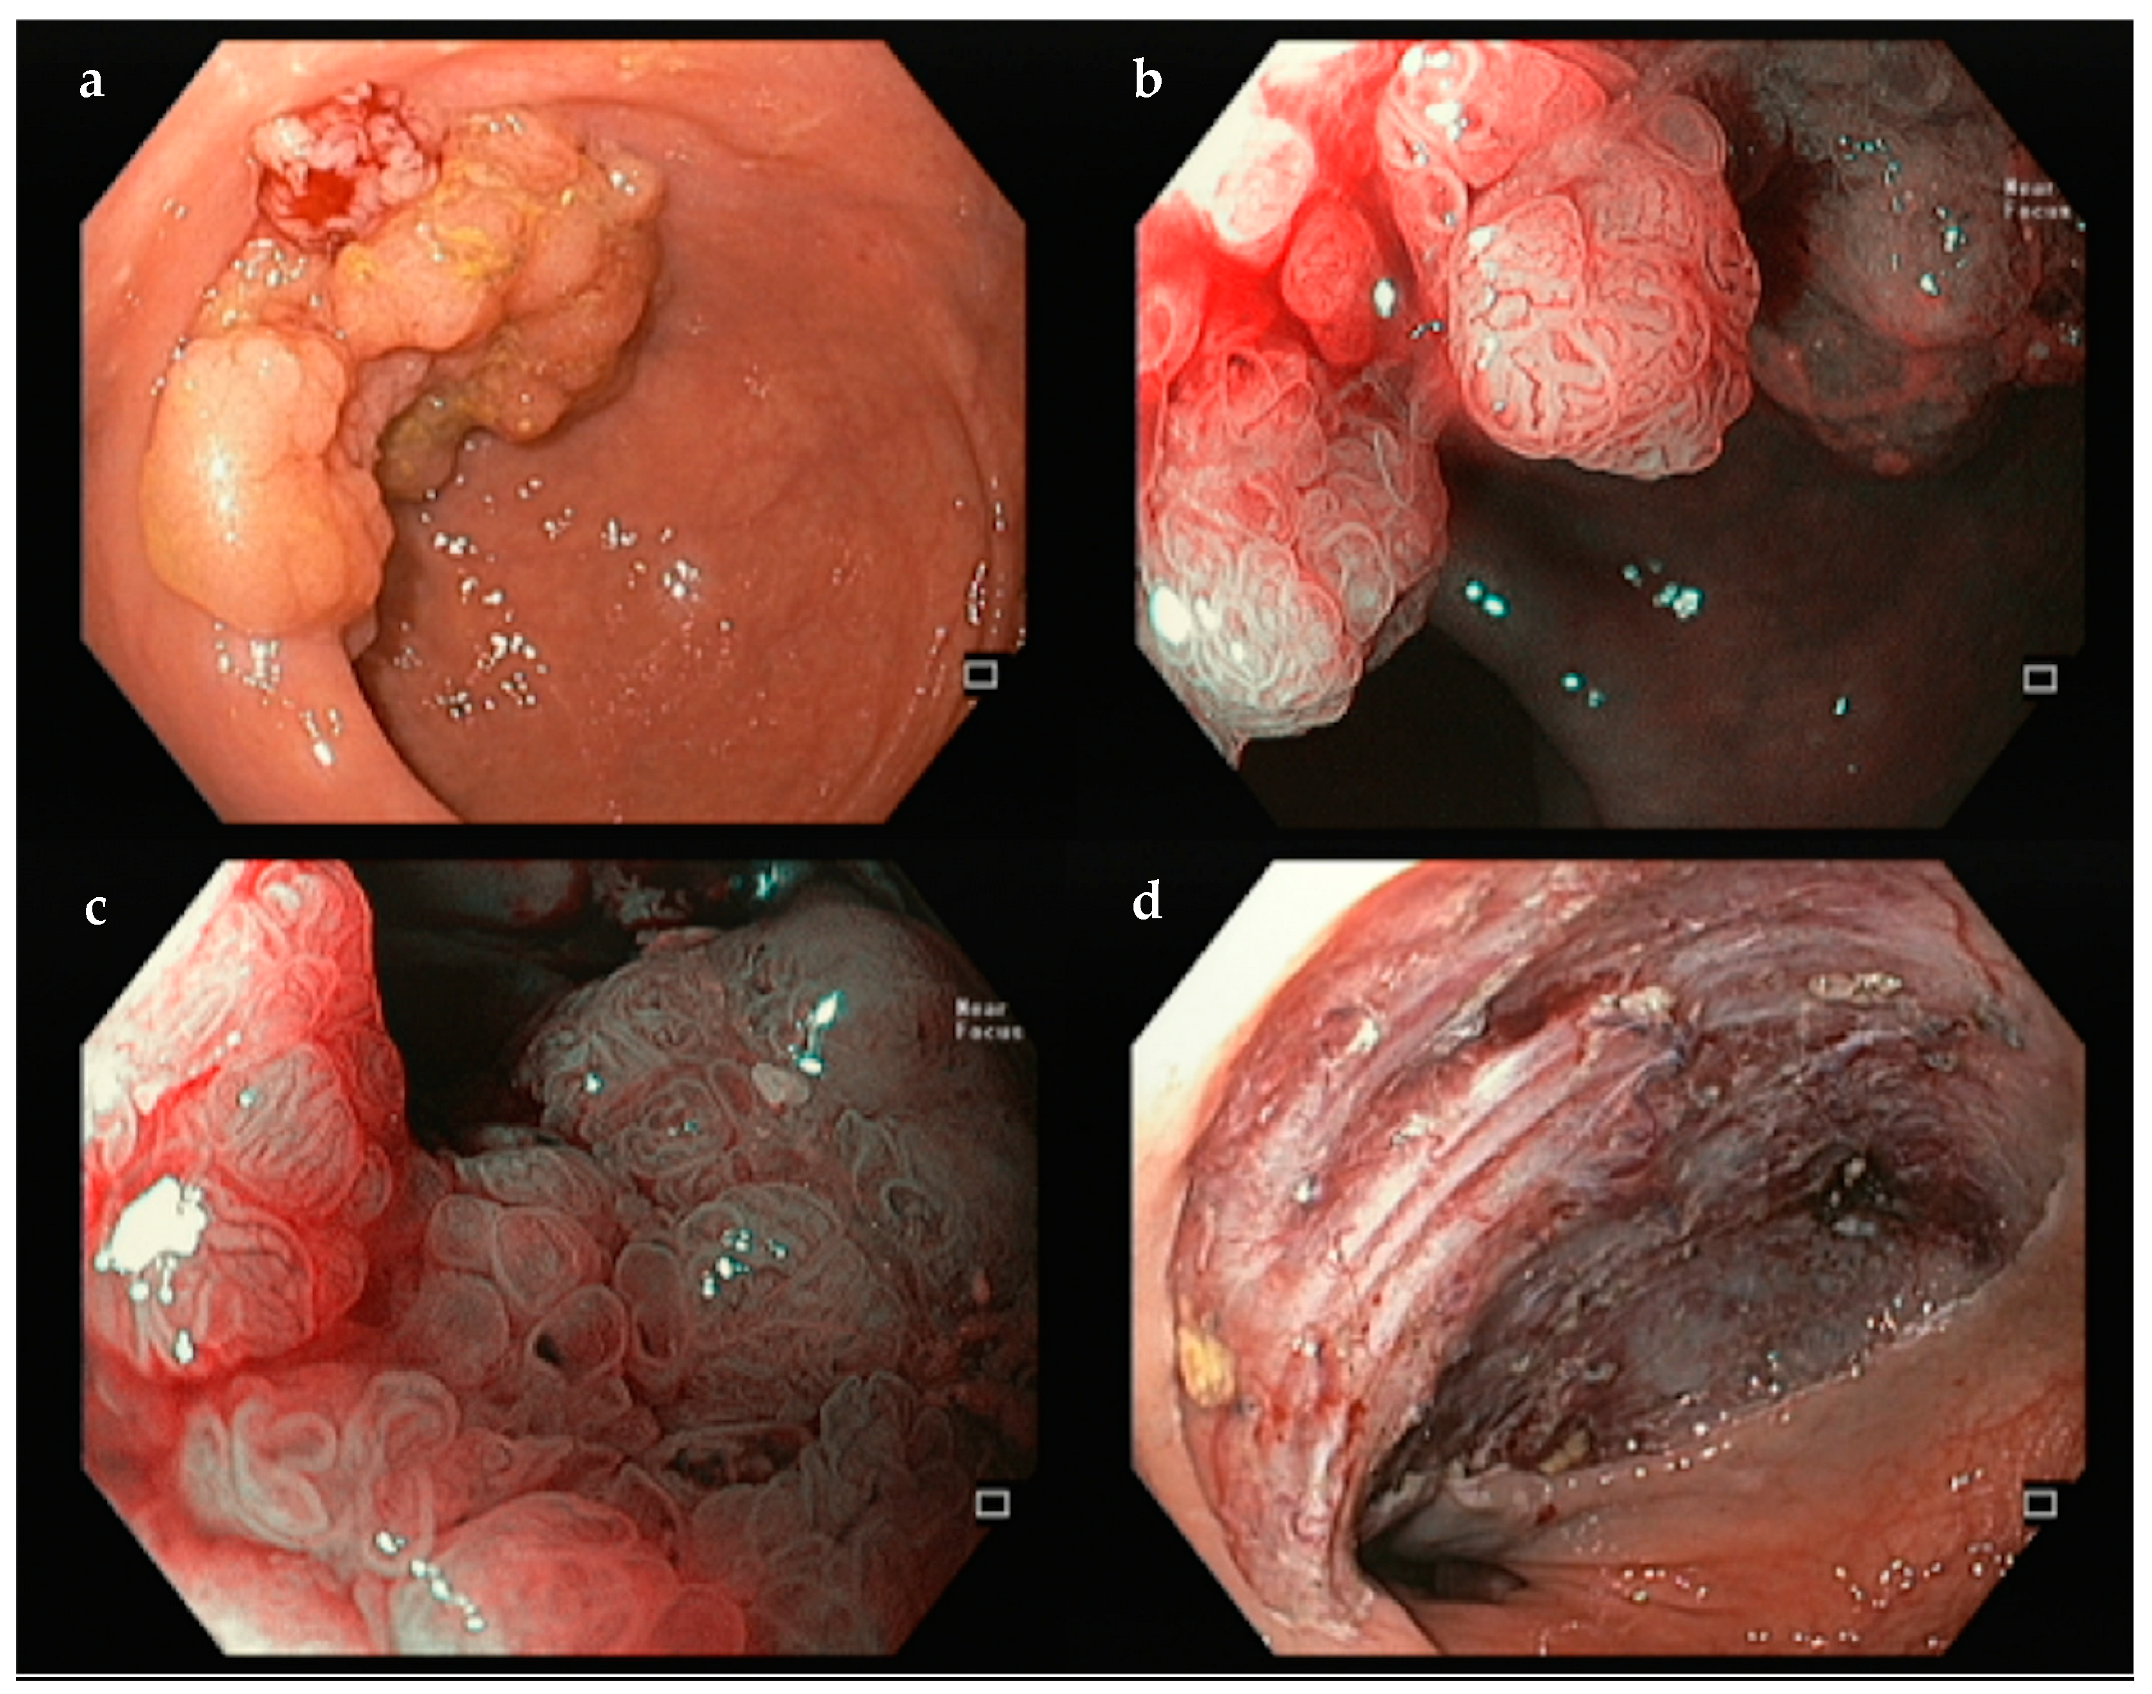

3.3. Colon and Rectum